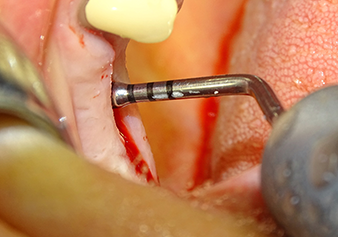

The I2A instrument (diameter 2.0 mm) was then used to perforate the sinus floor intermittently and on the smallest scale possible. This special piezosurgical method ensures that the Schneiderian membrane is not damaged. When the Z25P was used, the membrane was already lifted slightly by the coolant supplied via the instrument tip (Fig. 3). The coolant quantity was just 50% in order to avoid high pressure in the implant bed.

The Schneiderian membrane is carefully detached with the Z25P instrument (phase 1)

Fig.3: Following marking of the implant position and initial expansion of the bed, the Schneiderian membrane is carefully detached with the Z25P instrument (phase 1).